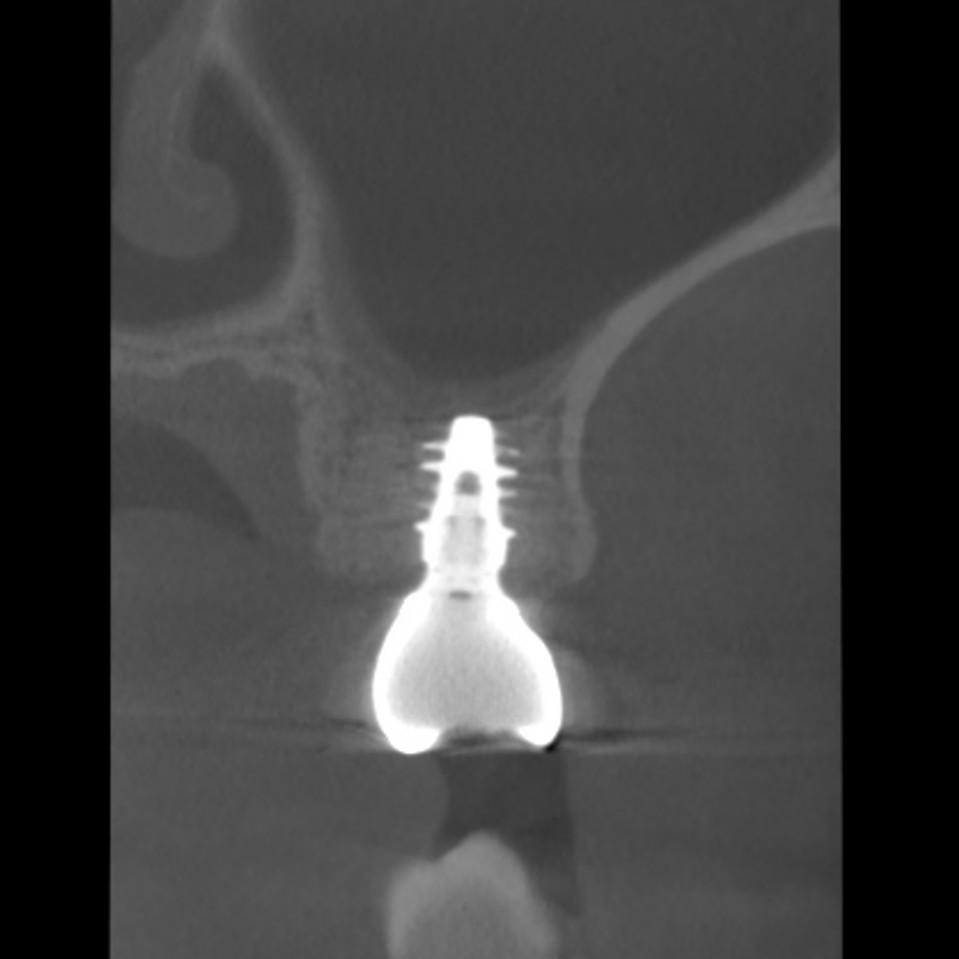

このように健康な歯が真っ二つに割れることはめったにないのですが、こうなると神経に触る様な強い痛みが出ますし、CTスキャンをとると上顎洞炎にもなっていました。

上の奥歯は上顎洞までの距離が短くインプラントが難しいことも多いのですが、即時埋入用に開発されたインプラントを使えば抜歯と同時にインプラント埋め込みまで行うことができると判断しました。

CTスキャンで確認してみても上顎洞炎もきれいに治っていることが分かります。